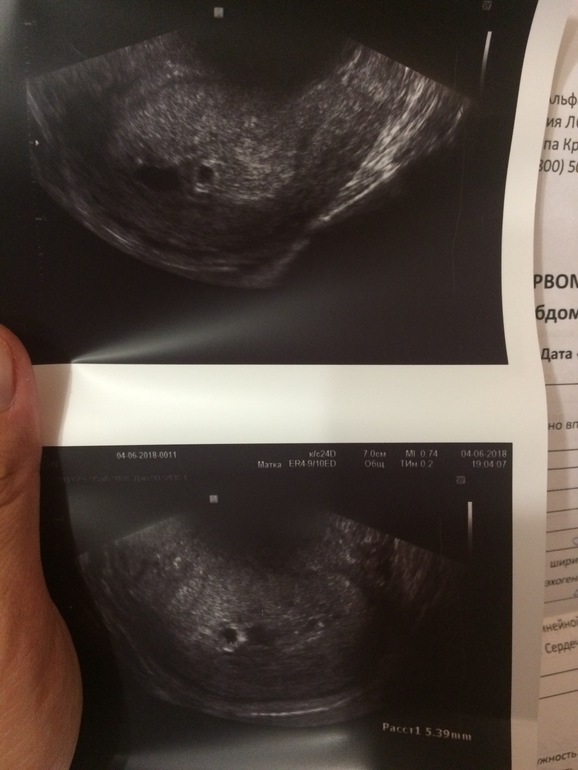

УЗИ, КТГ, доплерДевочки здравствуйте! Сходила на ещё одно УЗИ, в этот раз нашли пя (5мм), что соответствует сроку 4-5 недель, а у меня 6-7 по М... ( отставание на 2 недели) эмбриона пока не увидели... Врач сказала что пока переживать не о чем, тк 3 дня назад даже пя видно не было, динамика есть... впервые встретила врача оптимиста, которая не запугала, а наоборот подарила надежду)))) через неделю ещё одно УЗИ контрольное!

Насколько я поняла, в заключении УЗИ пишут акушерские недели, и для моего срока пя маленькое, в лучшем случае поздняя О, в худшем ЗБ, но об этом я не думаю))